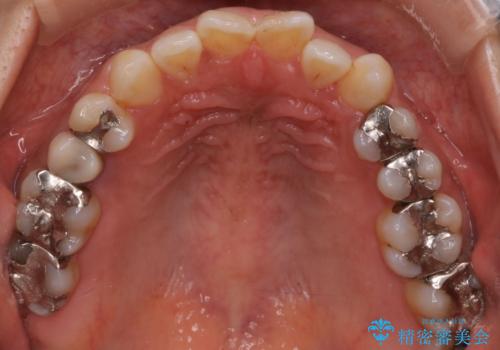

【インビザライン】前歯の凸凹をなおしたい

- 前歯の凸凹を主訴に来院されました。

インビザライン にて治療を行い、歯並びの改善を行うことができました。